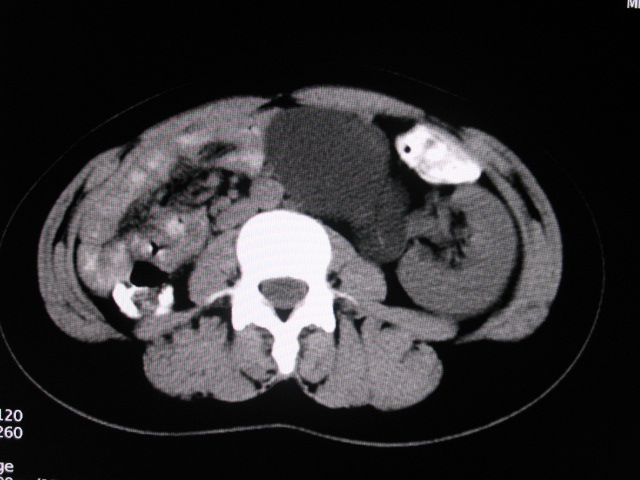

女,28岁,自觉腹部包块一年余

考虑左侧双肾盂双输尿管畸形,其中一输尿管末端梗阻(不排除异位开口可能)并相应之肾盂及输尿管明显扩张积水。

考虑左侧双肾盂双输尿管畸形,其中一输尿管末端梗阻并输尿管肠管样扩张盂曲、肾盂囊状扩张积水。

考虑左侧双肾盂双输尿管畸形,其中一输尿管末端梗阻(不排除异位开口可能,不知病人有无不自觉溢尿,有可能开口于阴道或宫颈,也可下端为盲端)并相应之肾盂及输尿管明显扩张积水。

术后证实是左侧双肾盂双输尿管畸形,巨输尿管巨肾盂症